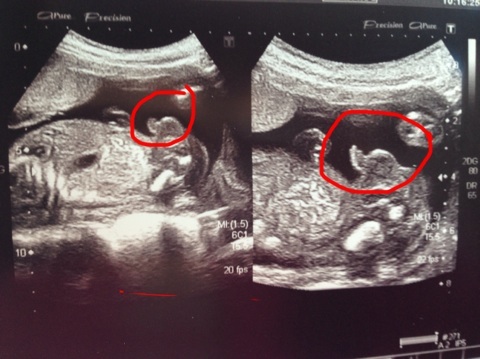

Клевый пуз))) и сыночек прям писюны уже такая)))))))))

Дааа))) писюн прям вышел хорошо на фото)))

классный отчетик,растите здоровенькими и крепенькими!Пузик у вас очень миленький)))и  длстоинство у вас ого го!Мужчинка)))

Ой как здорово!!!))) а я вот пожалела что не попросила сфотографировать половые признаки, чтобы особо неверующим показывать)))

Дааа... Сама не думала, что так четко получится)))